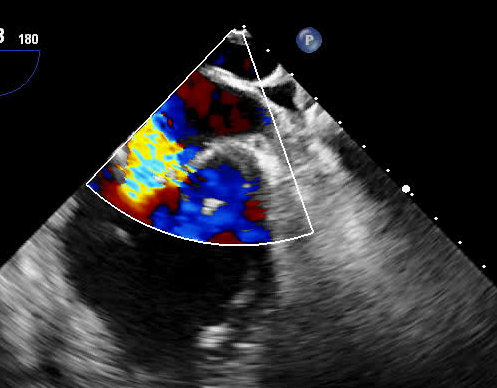

术前二尖瓣大量反流

术后微量反流

77岁的彭奶奶经心脏彩超显示二尖瓣大量反流,心脏明显增大,因为呼吸困难辗转多家医院就诊,经过抗心衰药物规范治疗后仍不能缓解症状。以往该类患者有两种治疗方式:一是实施传统外科换瓣手术,二是药物保守治疗。但对于高龄、集多种老年疾病于一身的患者,实施外科手术需要开胸并在体外循环下进行,风险极高;药物治疗仅能改善其心衰症状,但治标不治本,会导致心衰反复发作。

术前,科室组织多学科会诊,由心脏大血管外科、心内科、麻醉科等多位专家共同讨论并一致认为,老人二尖瓣病变严重,同时合并有冠心病、心律失常、心功能不全等多种高危因素,已不适用外科手术,在微创下不开胸实施二尖瓣钳夹术是最佳选择。经手术团队充分缜密的术前准备,在超声引导下器械经股静脉穿刺房间隔,将MitraClip系统送入患者左心房,到达二尖瓣反流处,在经食道超声及DSA引导下,术者通过评估二尖瓣反流位置、抓捕位置、反流程度,精准夹合,成功植入2个二尖瓣夹。二尖瓣从术前的大量反流减轻到微量反流,肺静脉的逆流完全消失,血压从偏低恢复到正常状态,第二天即下床,术后第5天顺利出院。